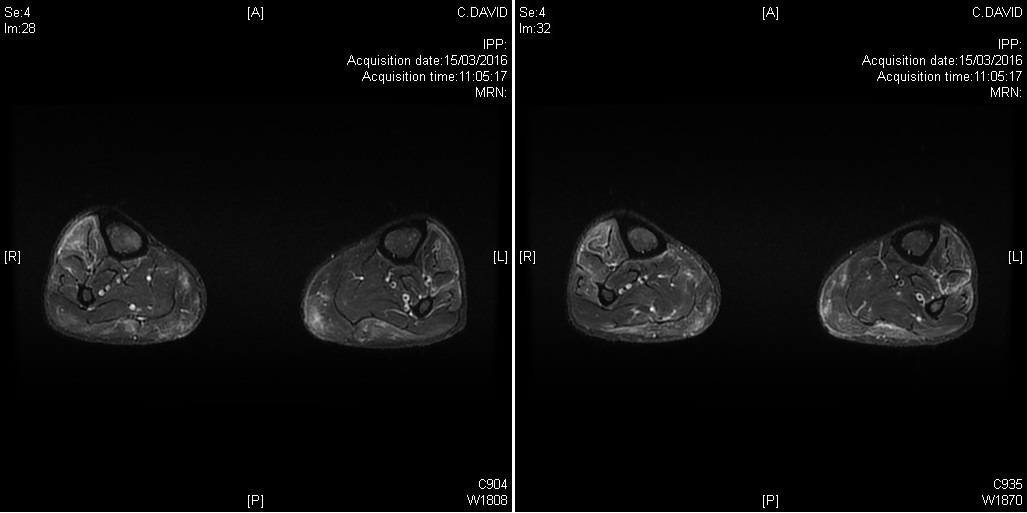

Hypersignaux T2 des muscles de la jambe dans le cadre d'un tableau clinique de dermatomyosite à auto-anticorps négatifs, révélée par une atteinte brutale oedémateuse

Tableau clinique de polymyosite avec atteinte clinique et IRM des deux jambes